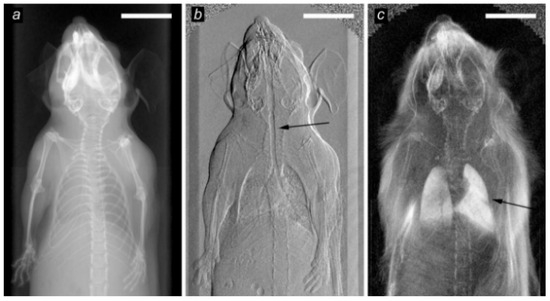

- Bech, M.; Tapfer, A.; Velroyen, A.; Yaroshenko, A.; Pauwels, B.; Hostens, J.; Bruyndonckx, P.; Sasov, A.; Pfeiffer, F. In-vivo dark-field and phase-contrast x-ray imaging. Sci. Rep. 2013, 3, 3209. [Google Scholar] [CrossRef]

- Scherer, K.; Yaroshenko, A.; Bölükbas, D.A.; Gromann, L.B.; Hellbach, K.; Meinel, F.G.; Braunagel, M.; Bergens, J.V.; Eickelberg, O.; Reiser, M.F.; et al. X-ray dark-field radiography in-vivo diagnosis of lung cancer in mice. Sci. Rep. 2017, 7, 1–8. [Google Scholar] [CrossRef]